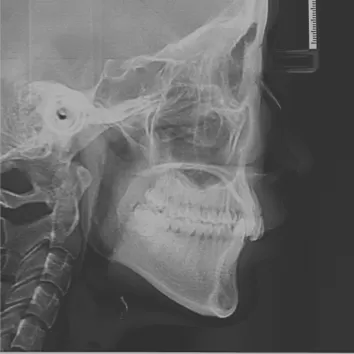

Rayons X avant le traitement

[Radiographie panoramique/Céphalogramme latéral]